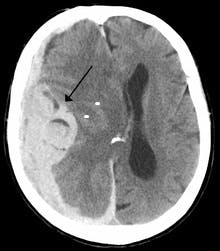

Dr. Jayadeepa, a practicing radiologist in Bangalore, India, shared the results of a study that she conducted in her local hospital, under the headline, “Automated AI Detection and Measurement of Midline Shift on Head CT Scans in an Emergency Teleradiogy Set-Up.” As the Wikipedia entry on midline shift explains, “Midline shift is a shift of the brain past its center line. The sign may be evident on neuroimaging such as CT scanning. The sign is considered ominous because it is commonly associated with a distortion of the brain stem that can cause serious dysfunction evidenced by abnormal posturing and failure of the pupils to constrict in response to light. Midline shift is often associated with high intracranial pressure (ICP), which can be deadly. In fact, midline shift is a measure of ICP; presence of the former is an indication of the latter. Presence of midline shift is an indication for neurosurgeons to take measures to monitor and control ICP. Immediate surgery may be indicated when there is a midline shift of over 5 mm. The sign can be caused by conditions including traumatic brain injury, stroke, hematoma, or birth deformity that leads to a raised intracranial pressure.”

“In our teleradiology setup that reads over 300 PET CT head scans a day,” Jayadeepa told her audience, “it was very important to prioritize critical findings, such as intracranial hemorrhage, acute infarcts, mass effect, and midline shift.” As a result, she noted, “We looked at 163 non-contrast pre-operative non-contrast adult CT exams of the head. We found 93 cases positive for midline shift of more than 3 mm and 70 cases negative for midline shift of 3 mm.” She and her colleagues set the algorithm to flag an alert when a midline shift of more than 3 millimeters was detected. She and her colleagues found an accuracy of 95.15 percent.

The practical impact of this was significant. “The immediate detection and accurate measurement of midline shift on head CT exams is key to prompt patient triage and management in the emergency setting,” Jayadeepa explained. “An AI algorithm demonstrated promising results in both detection and quantification of midline shift, thereby allowing for prioritization of radiologist review, accelerated critical value communication, and enhanced patient care.”